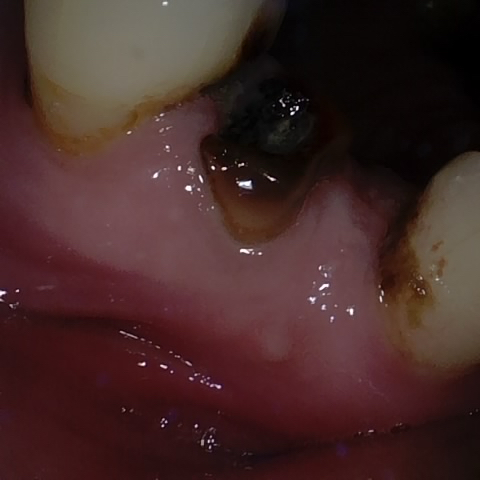

Annotated as "Good"